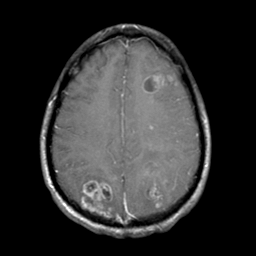

Sarcoma, MR Study #1 mr-gad -- Slice #17

[Home][Help][Clinical] Slice 17